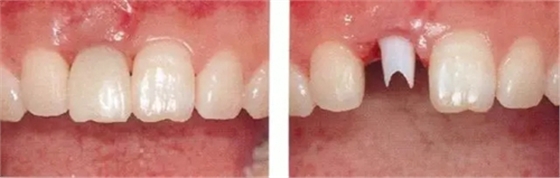

▲圖44-15,16

▲圖44-17,18

佩戴最終修復(fù)體時的正面口內(nèi)照和X光牙片。取得了很好的美觀狀態(tài)。

▲圖44-19,20

初診時和佩戴最終修復(fù)體時的狀態(tài)。適當修正牙冠形態(tài)后,恢復(fù)了前牙的美觀性。

▲圖44-21

6年后的狀態(tài)。